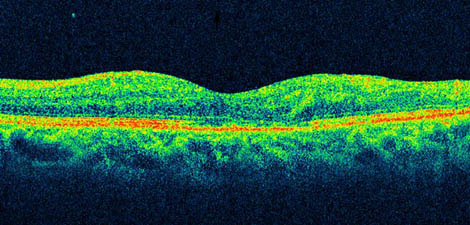

網膜の構造は,

感覚網膜の基本構築として9層 ということであるが,部位により特徴がある.端的に観察できるのが黄斑を通る水平断と思われる.

すなわち,

⒜ 黄斑・中心窩:

網膜外層(神経上皮層)のみということで内顆粒層より内側の成分はない.例えば,右図の組織図は神経節細胞層まで入っており中心小窩から少しずれた部分のセクションとわかる.

黄斑部,特に中心窩は視細胞のみ(神経上皮層),ということで,構成要素を網膜10層 でいうと内境界膜,外網状層,外顆粒層,外境界膜,視細胞層,網膜色素上皮層である.

網膜とOCT画像との対応

⑴.眼底構造物では,

神経線維層・各網状層で中反射〜高反射,

神経節細胞層・各顆粒層で低反射(攪乱 ??,

外境界膜より深部では低反射〜高反射層が観察される.

⑶.網膜外層,すなわち視細胞-網膜色素上皮部は,外境界膜を含め四層の中〜高反射層が認識されている.

⑷.右OCT図で,外層は,

ⓐ中反射:外顆粒層下部の反射線は外境界膜(ELM)と見做される.ただしMüller細胞は頂部細突起(微絨毛)が外境界膜を超えて視細胞間隙に伸びていることで,微絨毛を含めた反射信号とする研究者もいる.

次の低反射層は視細胞内節に相当する.または,myoid zone.

ⓑ高反射:IS-OS line.視細胞の内節 IS と外節 OS の境界線junctionに相当する.組織での結合繊毛部とは一致しないらしく,内節外端のミトコンドリアが多く集積している部分(エリプソイド部)として ellipsoid zone と呼ぶことが提唱されている.ただし,接合部外節(結合部・接合面)では反射を生じるインピーダンスがミトコンドリアよりも大きいことで,従来のIS-OS lineは妥当とする研究者もいる.視細胞の健常性を示すといわれ,外節の消失・再生がみられる病態からすれば,高反射を示す細胞膜の存在は理にかなっている.

次の低反射層は視細胞外節に相当する.中心窩部は錐体視細胞の形状の特徴として,わずかな膨らみ(foveal bulge;前方隆起)がある.

ⓒ高反射:COST line.錐体外節の終末端(COST;cone outer segment tip)で色素上皮細胞の長い絨毛が錐体先端を受け止めるような構造(cone sheath)の部分(右組織図▼)と考えられている.中心窩(bulge部)では長い錐体外節のため,錐体-網膜色素上皮の篏合構造の描出は不鮮明である.

ⓓ高反射:網膜色素上皮層.通常は一本の高反射ラインになるが,解像を上げると高反射-低反射-高反射の集合体(網膜色素上皮-ブルッフ膜複合体 complex)として観察できる.疑似カラー画像では一般に,橙色ラインとその下の緑色ラインの境界部分が,Bruch膜にほぼ一致するようである.これは色素上皮剝離の際に一本の高反射線として描出される.